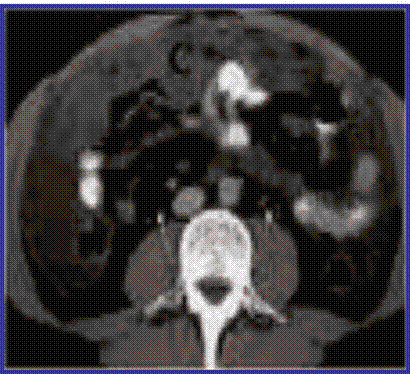

En la TAC de abdomen con contraste vía oral se observó marcado engrosamiento del peritoneo visceral y parietal en todo el abdomen, el cual englobaba todas las estructuras abdominales, y tenía una densidad de aproximadamente 26 UH, sospechándose la existencia de líquido ascítico, pero escaso y muy denso, predominando mayormente el engrosamiento y las masas descritas. Existían adenopatías intraperitoneales, peri aórticas y peri pancreáticas, así como nódulos superficiales umbilicales que impresionaban secundarios. (Figura 3).